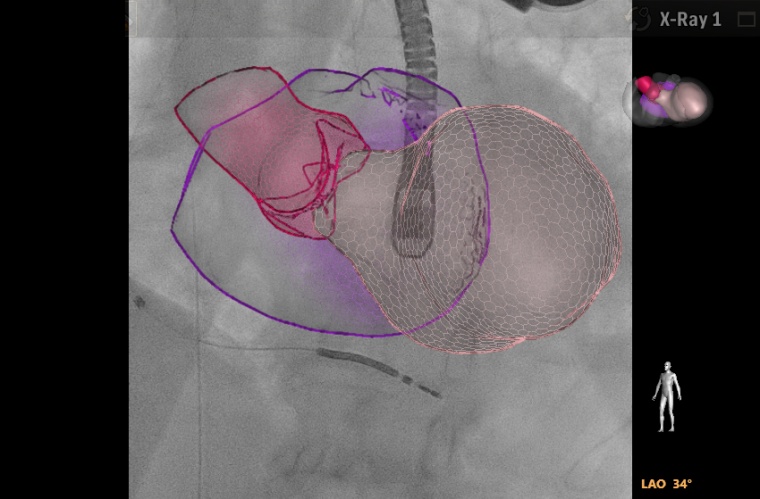

Mehr Qualität bei kardiologischen Interventionen

Aufgrund der immer höheren Lebenserwartung leiden auch immer mehr Deutsche an Herzklappenerkrankungen. In den Jahren von 1995 bis 2016 ist die Zahl der stationären Krankenhausaufnahmen wegen defekter Herzklappen um rund 70 Prozent gestiegen. Zugleich hat sich die kathetergestützte Behandlung von Herzklappenerkrankungen bei Patienten mit hohem Operationsrisiko als Alternative zur offenen Herzchirurgie etabliert, da sie eine niedrigere Mortalität im Krankenhaus und nach 30 Tagen aufweist sowie eine kürzere Verweildauer bedeutet. Um die Qualität bei der interventionellen Klappentherapie zu verbessern, setzt Dr. Ralph Stephan von Bardeleben KI in der Bildfusion ein. „Ein Bild ist kein Portrait, sondern eine Ansammlung von Daten. Diese Daten müssen wir nutzbar machen. Mithilfe von künstlicher Intelligenz können wir Informationen extrapolieren und dadurch relevanten Patientennutzen generieren“, erklärte der Oberarzt Herzkatheter am Zentrum für Kardiologie der Universitätsmedizin Mainz. Die Zusammenführung von statischen 2D-Bildern aus der Fluoroskopie und dynamischen 3D-Bildern aus der Echokardiographie mache es möglich, anatomische Strukturen im schlagenden Herzen zu markieren und diese während der Intervention ohne Einsatz von Kontrastmittel rasch aufzufinden. Dadurch verringere sich die Prozedurzeit. „Bildfusion eröffnet den neuen virtuellen herzchirurgischen Blick des interventionellen Kardiologen“, so Bardeleben.